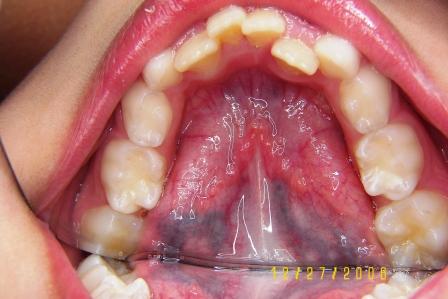

Crossbite - before and after: